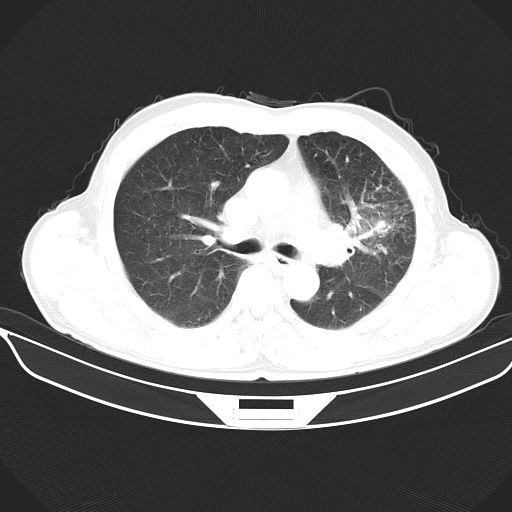

以下是引用心路寻觅在2010-3-1 10:23:00的发言:[br]1、考虑左肺上叶周围型肺癌[br]2、右上肺陈旧性病灶。[br][br][本贴已被 心路寻觅 于 2010-3-1 10:40:18 修改过]

以下是引用shuiyuan在2010-3-1 10:45:00的发言:[br]考虑左肺上叶中心型肺癌伴阻塞型炎症,邻近胸膜受侵。